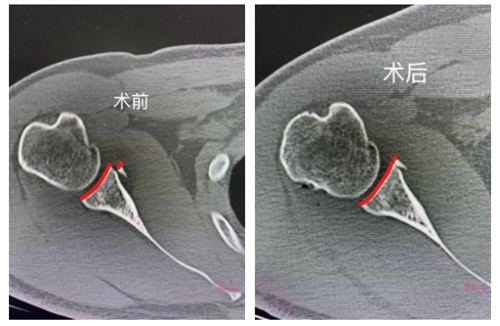

(骨折块精准复位)

李云飞指出,以往此类骨折手术因位置较深,常需较大切口,创伤大、恢复慢。而如今,随着关节镜微创技术的成熟,医生仅需通过几个微小孔道即可直达病灶,利用锚钉与缝线精准复位并固定骨折部位,显著降低手术创伤,加速患者康复。